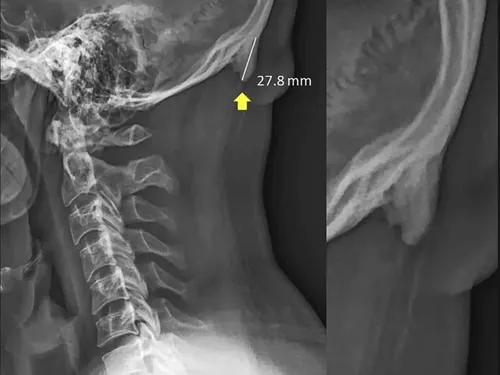

ciocuri osoase in spatele craniului/Foto: Captura Twitter

Noi cercetări în domeniul biomecanicii sugerează că tinerii au început să dezvolte o serie de excrescențe osoase foarte similare cu coarnele în spatele craniilor - ciocuri osoase cauzate de de înclinarea înainte a capului, care schimbă greutatea dinspre coloana vertebrală la mușchii din spatele capului, producând creșterea osului în zona în care se conectează tendoanele și ligamentele. Transferul de greutate care cauzează acumularea poate fi comparată cu modul în care pielea se transformă într-o bătătură ca răspuns la presiune sau frecare.

Rezultatul este un cârlig sau un corn care se ivește din craniu, chiar deasupra gâtului.